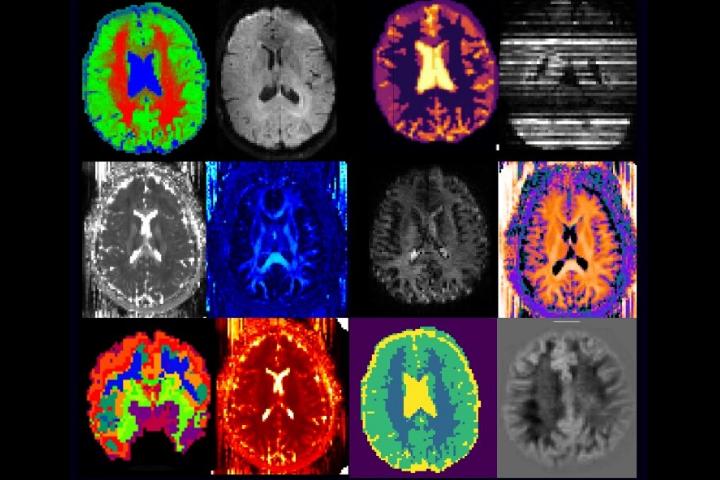

The long-term memory of music, in the salience network of the brain, remainsintactuntiltheverylaststagesofAlzheimer’sdiseaseprogression beforeitattacksthebrainstem,resultinginagreaterlikelihoodofmusicto evoke memories even in later stages of the disease; researchers in the UniversityofUtahHealthwhoplayedpersonalisedplaylistsforparticipants with dementia under a functioning MRI found that music activated whole areas of the brain, causing regions to communicate, including the visual network,thesaliencenetwork,theexecutivenetworkandthecerebellarand corticalcerebellarnetworkpairstoallshowingsignificantlyhigherfunctional connectivity. Using individualised playlists are a crucial part of music therapy,withstudiesshowingthatmusicenjoyedfromtheagesof10to30 yearsoldismoreenduringandrekindlingforpatientswithAlzheimer’s.